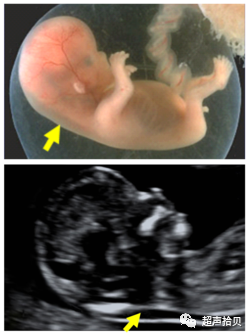

• 约5%的病例中,胎儿颈部会被脐带环绕。研究已发现,NT的测量值会因此而增加

• 在这样的病例中,在脐带上方或下方测量NT结果会有所不同。计算风险的时候,取上方和下方的平均值比较合适。